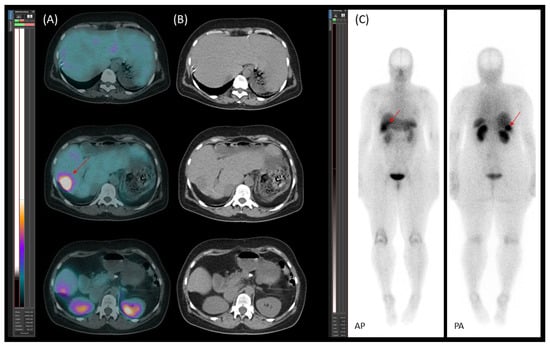

Starting on 21 January 2023, the patient underwent four cycles of [177Lu]Lu-DOTA-TATE therapy due to disease progression despite treatment with somatostatin analogue (SSA). The therapy led to a reduction in both the number and metabolic activity of somatostatin receptor (SSTR)-positive lesions (Figure 8).

Figure 8. [177Lu]Lu-DOTA-TATE therapy response. Transaxial (A,B) SPECT/CT images and planar images (C,D) (AP—anteroposterior; PA—posteroanterior) obtained after the first (A,C) and fourth (B,D) therapy cycles with [177Lu]Lu-DOTA-TATE. The images demonstrate a reduction in both the number and activity of somatostatin receptor (SSTR)-positive lesions in the liver (red arrows), as well as a decrease in the size and activity of a para-aortic lymph node metastasis (blue arrow) following therapy.